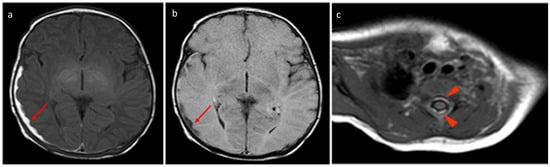

Figure 2. Birth-related SDH in a 9-day-old infant born spontaneously: (a) Right paramedian sagittal plane T1-weighted SE sequence—the presence of subdural hematomas with occipital (red arrow), parietal (green arrow), and cerebellar (yellow arrow) distribution. (b) Midsagittal plane T1-weighted SE sequence—similar finding in the spinal canal anteriorly in the cervico-dorsal tract (arrowhead). (c) SE T1-weighted sequence in the axial plane passing through the distal cervical tract—confirmation (arrowhead).

Figure 3. In the same patient in Figure 2, (a) FLAIR T2-weighted sequence in the axial plane at the level of the posterior cranial fossa—the subdural hematomas described in the bilateral retrocerebellar region (solid arrow) also appear hyperintense in this sequence, as in the late subacute phase (extracellular methemoglobin). (b) FSE T2-weighted sequence on the axial plane at the same 3a level—the known hematomas are difficult to appreciate in relation to the spontaneous hyperintensity. (c) SE T1-weighted in the midsagittal plane—the resolution of the hematomas described in Figure 2 and Figure 3 is observed in the follow-up examination.